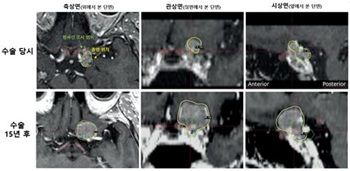

[그림1 : 55세 여성 환자의 시신경 인접 수막종 수술 당시(상단)와 15년 후(하단) MRI 영상. 수술 당시 시신경 보호를 위해 종양 일부에 방사선을 쏘지 않았으나(커버리지율 74.4%), 15년 뒤 과거 방사선을 피했던 부위에서 종양이 다시 자라났다(하단). 재발 확인 후 방사선을 5번에 나눠 쏘는 ‘다분획(저분할) 감마나이프 수술’을 시행해 16개월 후 시력 저하 없이 종양을 현저히 축소시켰다.]

가장 눈길을 끄는 것은 종양이 다시 자라난 위치다.

재발한 종양 대부분은 과거 수술 당시 시신경 보호를 위해 의도적으로 방사선을 덜 쏘았던 바로 그 부위에서 발생했다.